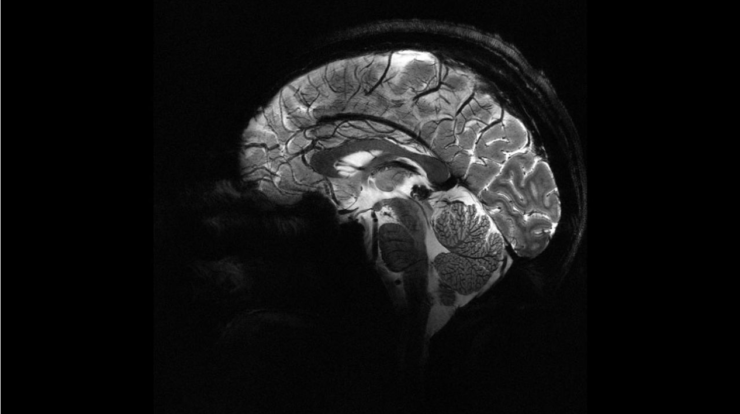

Uzmanlar, geleneksel beyin görüntüleme yöntemleriyle gözden kaçabilen küçük lezyonların, epilepsi tedavisinde kritik rol oynadığını belirtiyor. Yapay zekâ destekli sistem, MRI ve diğer görüntüleme verilerini analiz ederek bu gizli malformasyonları yüksek doğrulukla saptayabiliyor.